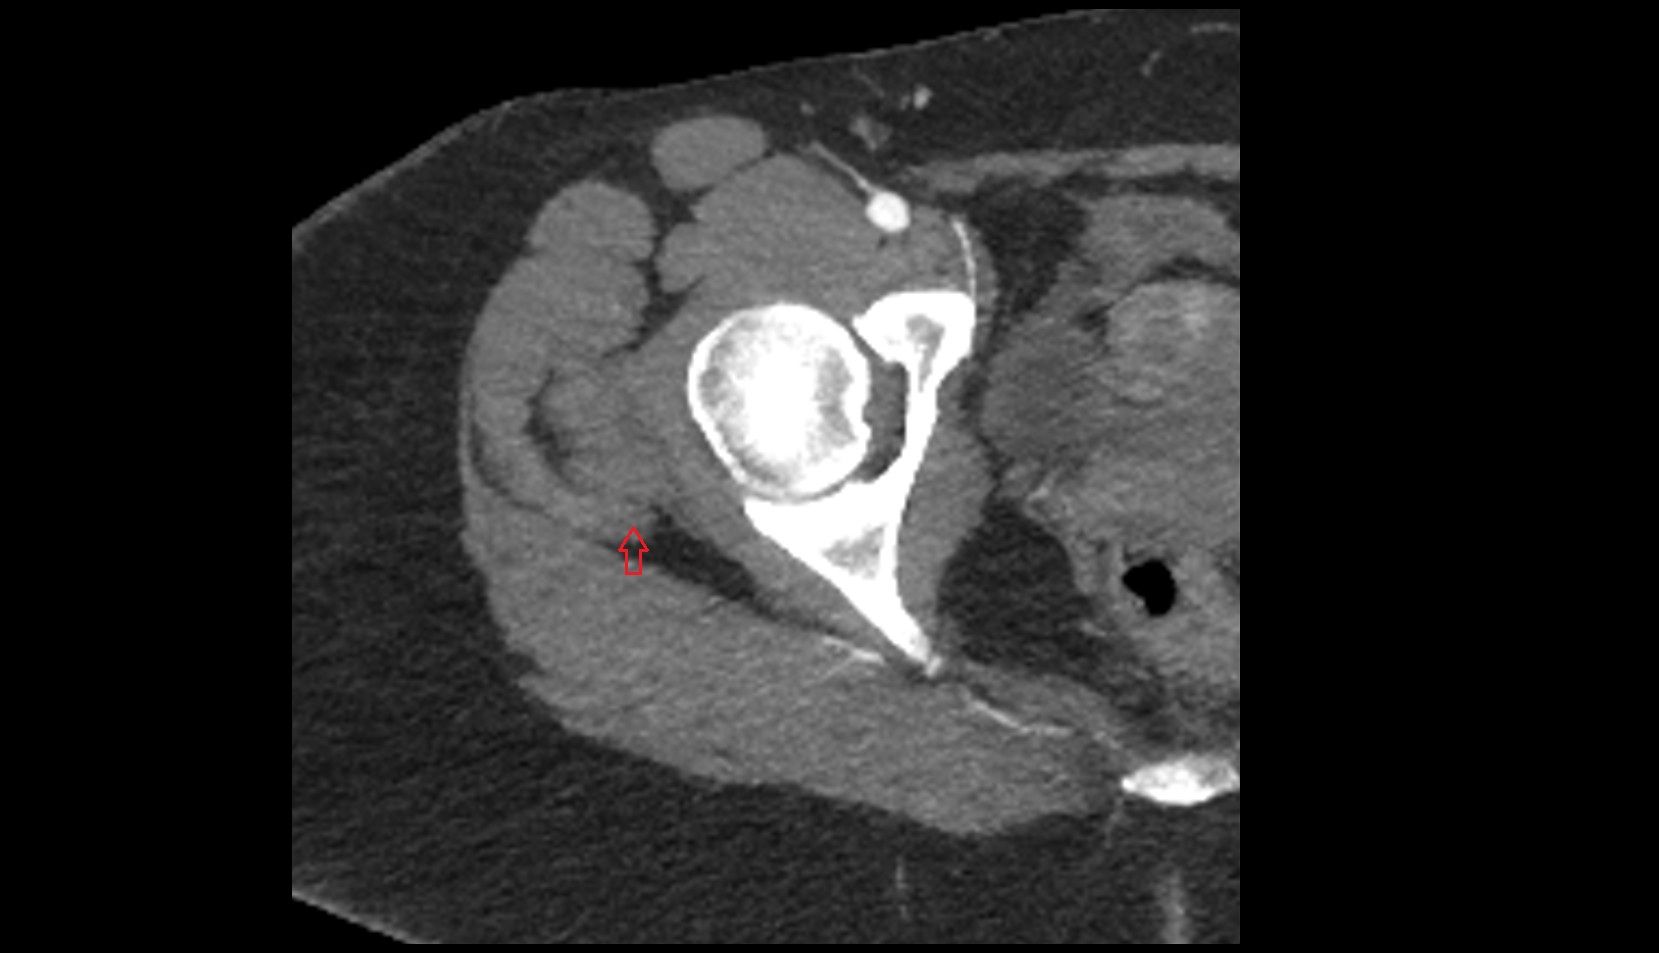

- Peripheral zone of prostate

- Anterior Fibromuscular Stroma of prostate

- Central zone of prostate

- Transitional zone of prostate